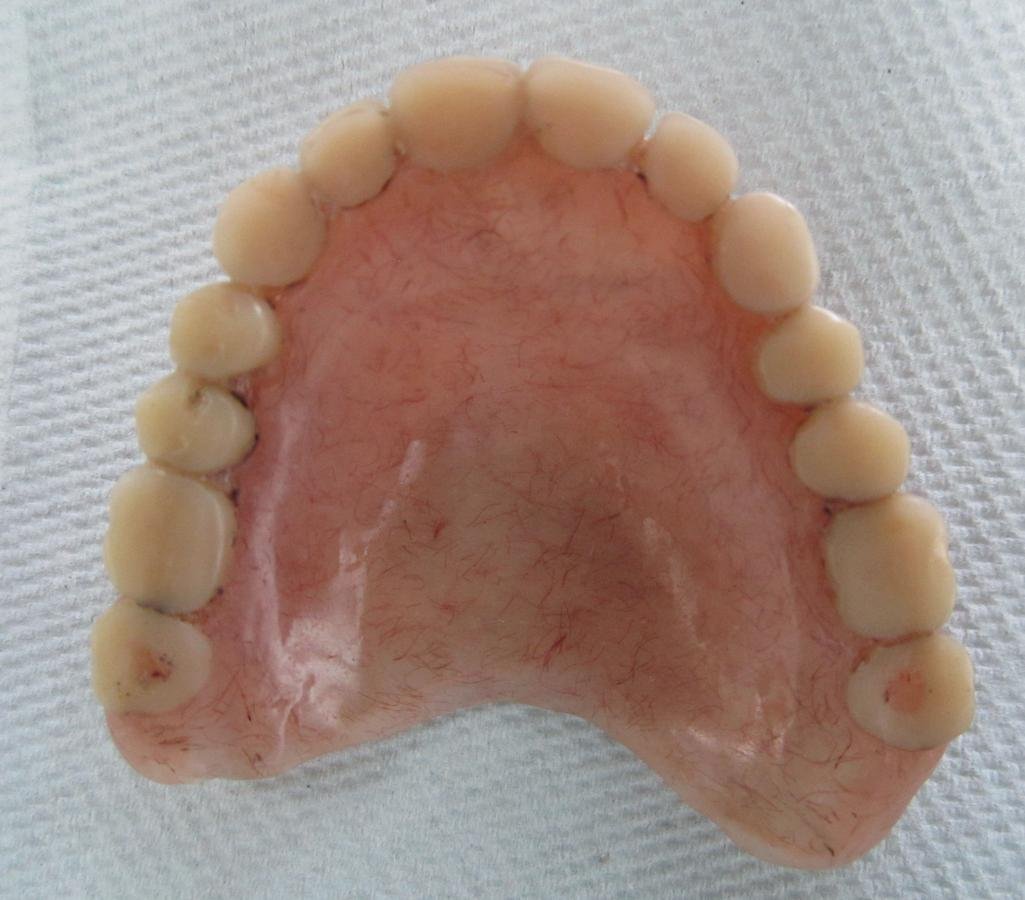

TRATAMIENTO FINAL

Prótesis total superior e inferior elaboradas con Eclipse